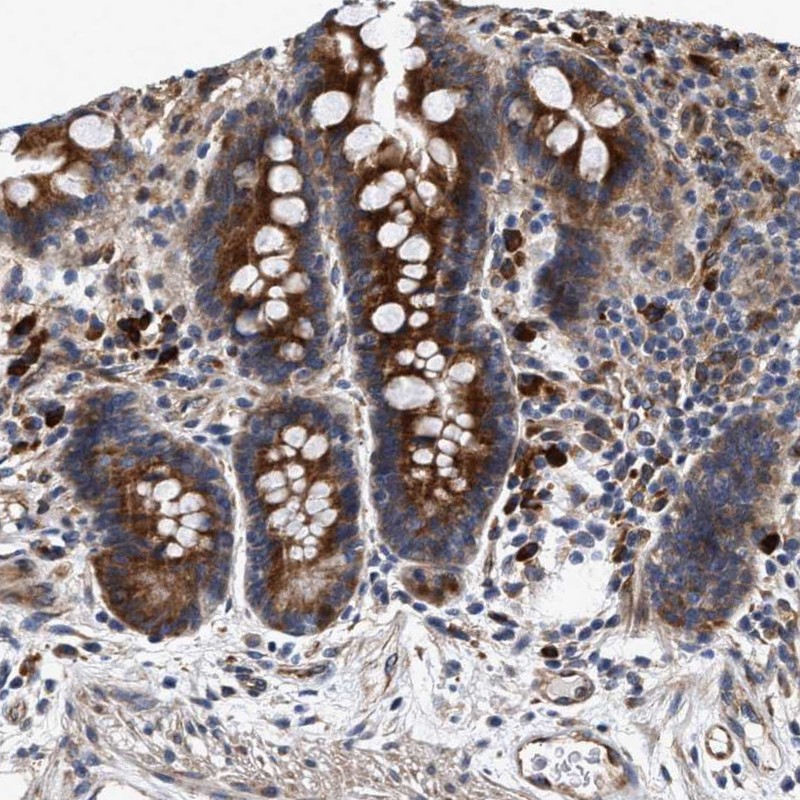

Immunohistochemical staining of human colon shows strong cytoplasmic positivity in glandular cells.